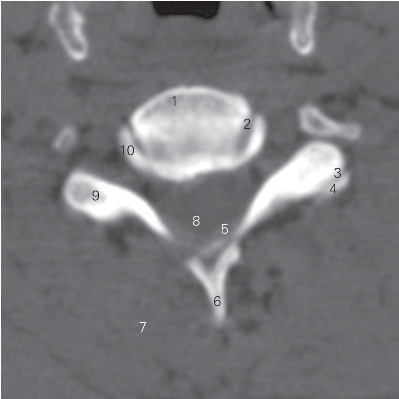

图1-2 经第5颈椎椎体的横断层CT图像(骨窗)

1 第5颈椎椎体 5th cervical vertebral body

2 钩椎关节 uncovertebral joint 3 关节突关节 zygapophysial joint

4 上关节突 zygapophysis superior 5 黄韧带 ligamentum flavum

6 棘突 spinous process 7 颈半棘肌 semispinalis cervicis

8 颈髓 cervical cord 9 横突 transverse process

10 椎体钩 uncus of vertebral body